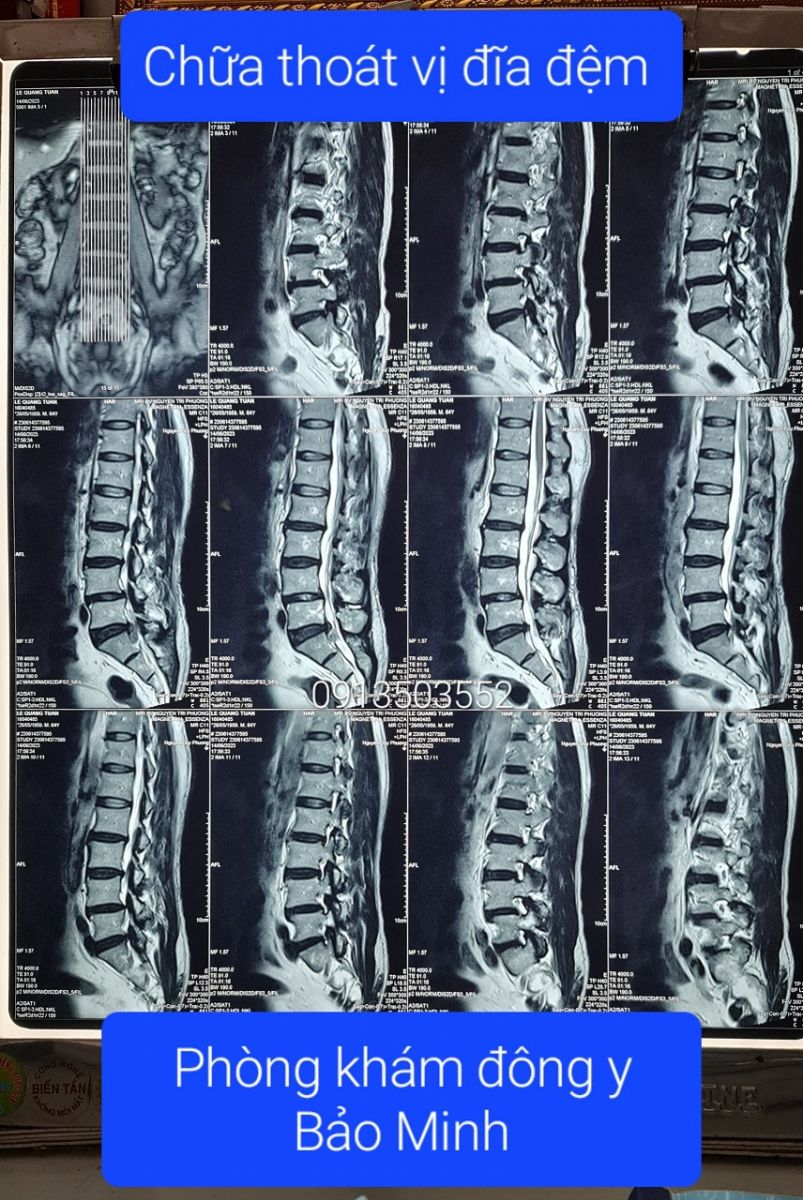

Thoát vị đĩa đệm L4 L5Thoát vị đĩa đệm L4 L5, kích thước 6mm, chèn ép vào rễ thần kinh L5 hai bên và gây hẹp ống sống (đường kính trước - sau #6mm)❮ đọc tiếp ❯